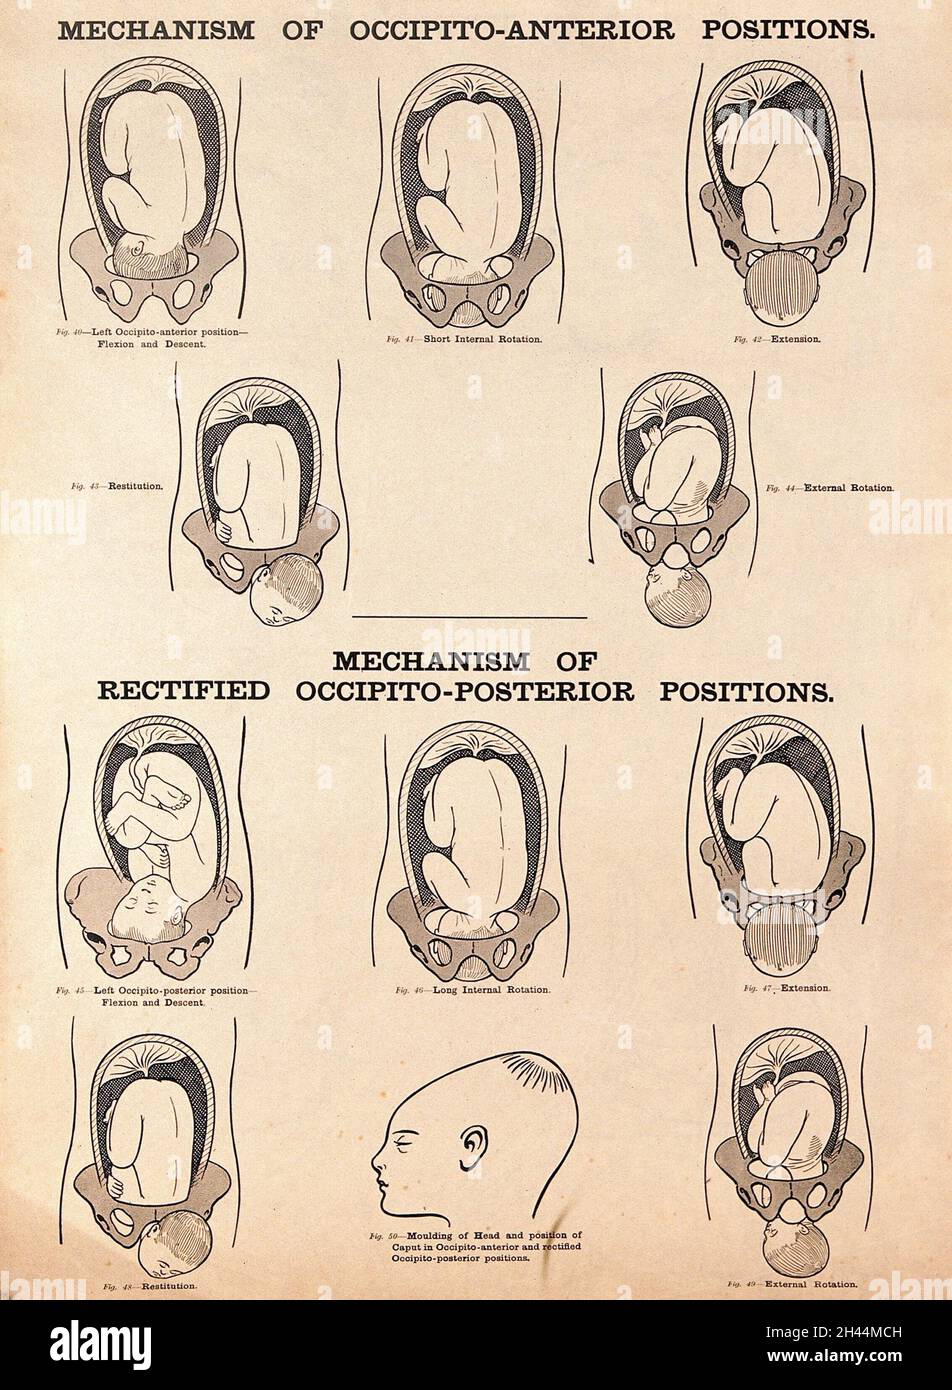

Mechanisms of occipito-anterior positions and rectified occipito-posterior positions of the foetus. Lithograph after W. F. Victor Bonney. Stock Photohttps://www.alamy.com/image-license-details/?v=1https://www.alamy.com/mechanisms-of-occipito-anterior-positions-and-rectified-occipito-posterior-positions-of-the-foetus-lithograph-after-w-f-victor-bonney-image450032033.html

Mechanisms of occipito-anterior positions and rectified occipito-posterior positions of the foetus. Lithograph after W. F. Victor Bonney. Stock Photohttps://www.alamy.com/image-license-details/?v=1https://www.alamy.com/mechanisms-of-occipito-anterior-positions-and-rectified-occipito-posterior-positions-of-the-foetus-lithograph-after-w-f-victor-bonney-image450032033.htmlRM2H44MCH–Mechanisms of occipito-anterior positions and rectified occipito-posterior positions of the foetus. Lithograph after W. F. Victor Bonney.